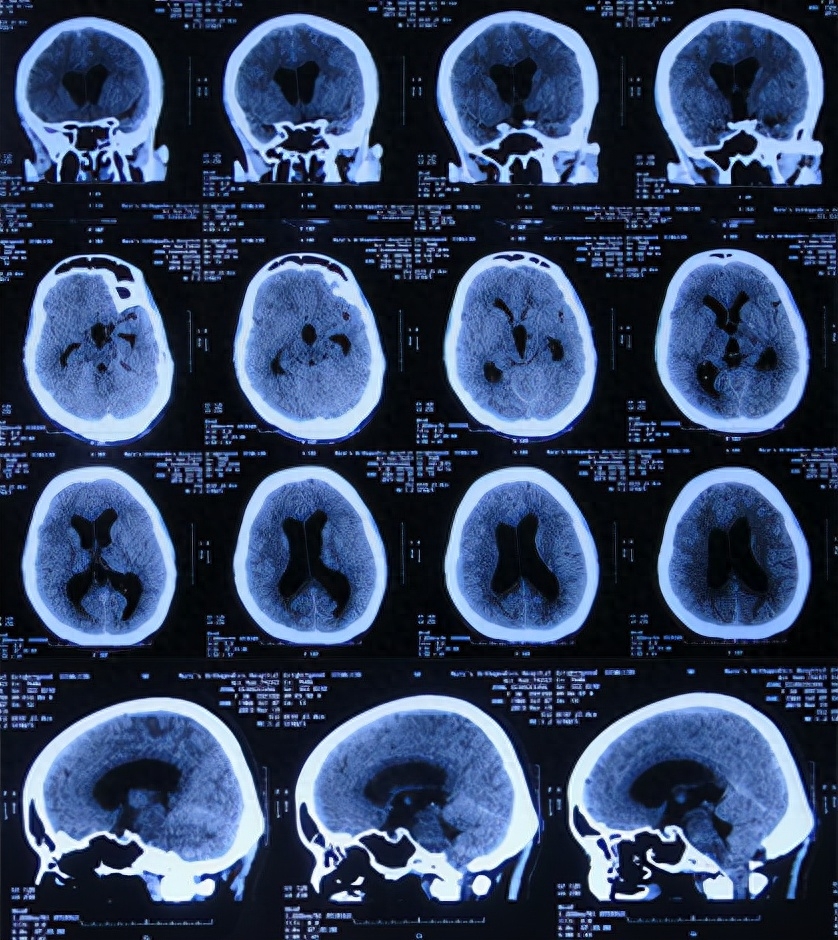

给予甘露醇治疗后10天即2019年2月24日,仍间断头痛和发热,查头颅CT(图-4)后,给予腰椎穿刺术。

图-4:2019年2月24日头颅CT

但腰椎穿刺术后头痛仅短暂缓解1天左右,在该院继续治疗8天,仍间断头痛发热,间断给予腰穿治疗,化验脑脊液白细胞高,曾先后3次查头颅CT(图-5、图-6、图-7)均示脑室并未明显扩张。

图-5:2019年2月26日头颅CT

图-6:2019年2月27日头颅CT

图-7:2019年3月5日头颅CT